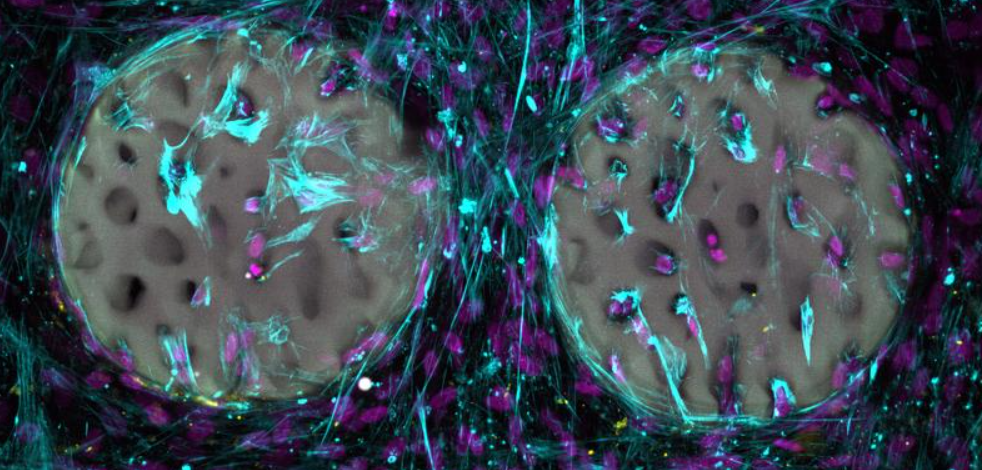

Ein gutes Zeichen: Knochenbildende Zellen (violett) haben ein Hydrogel, das wie Knochen strukturiert wurde, bereits besiedelt und Kollagen (hellblau) produziert. | Quelle: Xiao-Shua Qin | Copyright: ETH Zürich

In Labortests besiedelten knochenbildende Zellen (Osteoblasten) das strukturierte Hydrogel rasch, produzierten Kollagen und zeigten keine Schädigung durch das Material. Die Biokompatibilität wurde bestätigt. Als Vorlagen für die komplexen Strukturen dienten Aufnahmen aus der medizinischen Bildgebung.